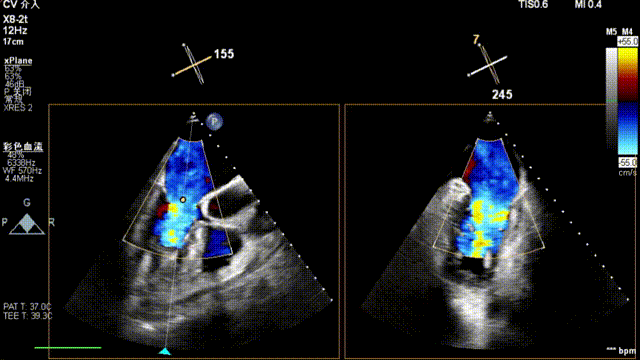

术中超声(关键步骤)

全麻后,二尖瓣夹合器系统在心前区的肋间切开3-4CM小切口,暴露心脏的心尖位置,送系统送入左心房,顺利到达病变二尖瓣区域。在经食道超声辅助下,术者通过反复评估二尖瓣反流位置、抓捕位置、反流程度,首先在2偏3区位置处于二尖瓣闭合线垂直进行巧妙夹合。在2区靠近3区位置处植入了1枚ValveClamp®MVC-IIf夹,最终评估评估反流降至轻度,平均跨瓣压差降至2mmHg,手术取得圆满成功。

最终在A3P2位置夹合,前叶夹合量10mm,后叶夹合量8mm,剩余瓣口面积3.45cm²,平均跨瓣压差2mmHg,反流基本消除。